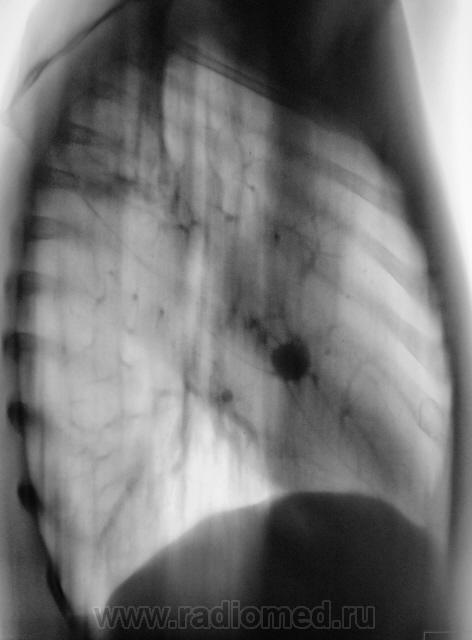

Томограммы в боковой проекции.

2 срез.

Думаю, больше данных за туберкулому. Интенсивность, структура, изменения фиброзно-очагового характера в окружающей ткани, в т.ч. подтягивание плевры. 90% за ТБС.

Доброго дня! И нет ничего удивительного в положительных посевах, в S2 справа нормальная такая туберкулема с участком просветления за счет распада и дренирующим бронхом, даже без ТГ видно, ежели б мокроту тщательнее смотрели (много значит опыт лаборанта) - скопически бы поймали КУМ,  а так посев только 2 мес. растет.

Туберкулома в S4.